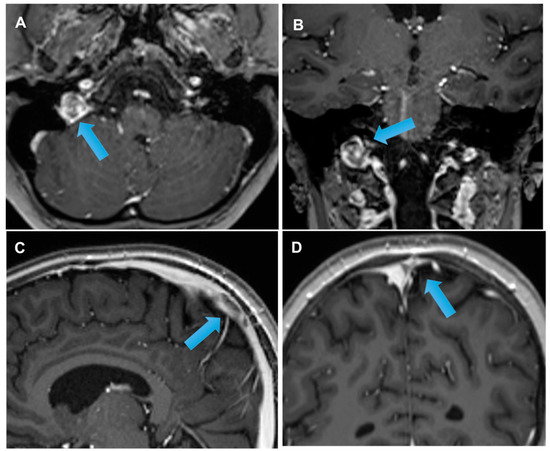

3.3. Stroke-like Migraine Attacks after Radiation Therapy

- Kerklaan, J.P.; Lycklama á Nijeholt, G.J.; Wiggenraad, R.G.J.; Berghuis, B.; Postma, T.J.; Taphoorn, M.J.B. SMART syndrome: A late reversible complication after radiation therapy for brain tumours. J. Neurol. 2011, 258, 1098–1104. [Google Scholar] [CrossRef] [PubMed] [Green Version]

- Rigamonti, A.; Lauria, G.; Mantero, V.; Filizzolo, M.; Salmaggi, A. SMART (stroke-like migraine attack after radiation therapy) syndrome: A case report with review of the literature. Neurol. Sci. 2016, 37, 157–161. [Google Scholar] [CrossRef]

- Armstrong, A.E.; Gillan, E.; Di Mario, F.J. SMART Syndrome (Stroke-Like Migraine Attacks After Radiation Therapy) in Adult and Pediatric Patients. J. Child Neurol. 2014, 29, 336–341. [Google Scholar] [CrossRef]

- Black, D.F.; Morris, J.M.; Lindell, E.P.; Krecke, K.N.; Worrell, G.A.; Bartleson, J.D.; Lachance, D.H. Stroke-Like Migraine Attacks after Radiation Therapy (SMART) Syndrome Is Not Always Completely Reversible: A Case Series. Am. J. Neuroradiol. 2013, 34, 2298–2303. [Google Scholar] [CrossRef] [Green Version]